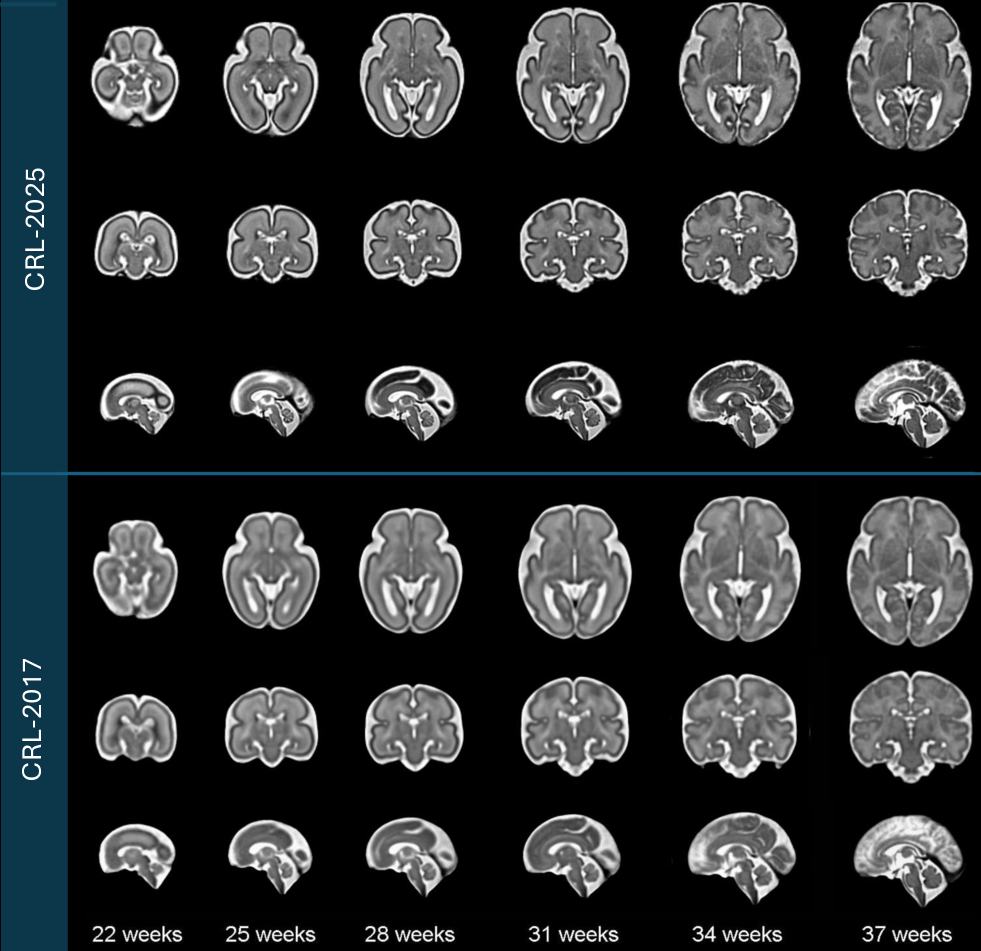

Fetal brain MRI scans were pre-processed following the procedures outlined in the Methods section. The processed images were then used to construct the spatiotemporal atlas according to Algorithm 1, which enables the generation of an unbiased average atlas at any continuous gestational age. Figure 3 displays axial, coronal, and sagittal views of the resulting atlas at representative gestational ages, alongside corresponding views from the CRL-2017 atlas for comparison [22]. The atlas shape and size complies with the older validated atlases, including the CRL-2017 atlas. Both visual inspection and quantitative analyses suggest that the CRL-2025 atlas much better preserves anatomical details and is sharper than the CRL-2017 atlas. For this, as shown in Table 1, we computed median edge sharpness to quantitatively assess the clarity of anatomical boundaries in each atlas. This metric, defined as the median gradient magnitude at anatomical edges detected within the atlas, reflects sharpness of typical tissue transitions. Across all gestational ages, CRL-2025 consistently exhibited higher median edge sharpness than CRL-2017, with differences ranging from +0.14 to +0.39. These results demonstrate that CRL-2025 provides more clearly defined anatomical boundaries throughout development, confirming its advantage for many applications such as atlas-based segmentation and analysis.

Refer to caption

Figure 3: Comparison of spatiotemporal fetal brain MRI atlases ( CRL-2025 vs. CRL-2017) at six representative gestational ages: 22, 25, 28, 31, 34, and 37 weeks. Axial, coronal, and sagittal views are presented for each atlas at each age.